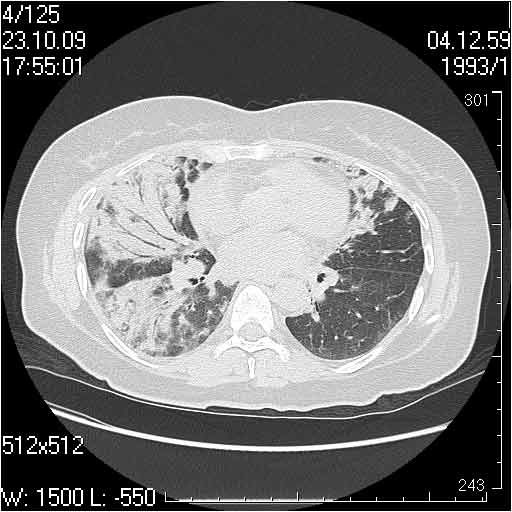

Случай №2

Мужчина 54 лет

Случай 2: картина патологических изменения довольно типична: GGOs & thickened interlobular septas = "crazy paving" sign. Наличие плотностей по типу матового стекла в сочетании с утолщением междолевых перегородок, даёт признак булыжной мостовой; на первом месте будет стоят диагноз альвеолярных протеиноз.